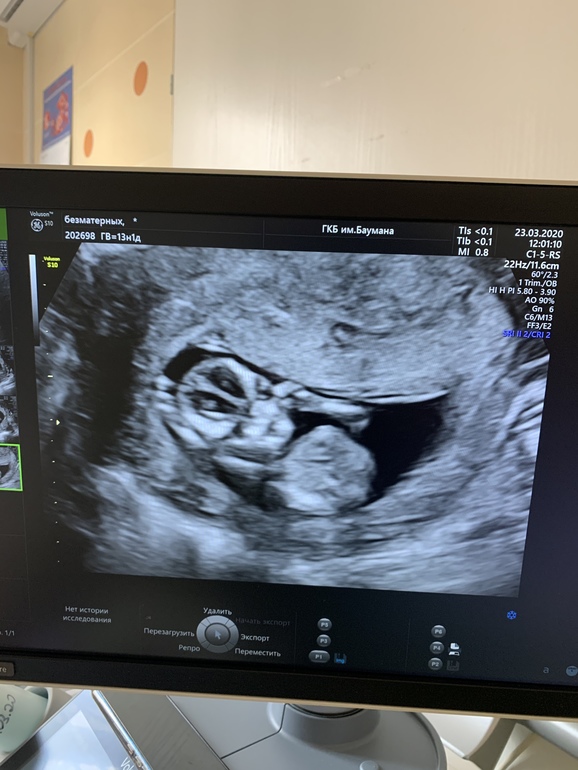

Девочки, привет!) сегодня была на первом скрининге, от эмоций забыла спросить узистку видно ли уже пол. Но сделала фотки. Начала вглядываться и кажется нашла какую-то пипирку. Опытные девушки, Как думаете это он или она, или вообще не видно и это что-то другое?

Срок 13 недель и 1 день.

Ещё во время скрининга ребёнок повернулся лицом к узи и я немного испугалась маленького пришельца, не ожидала такое увидеть